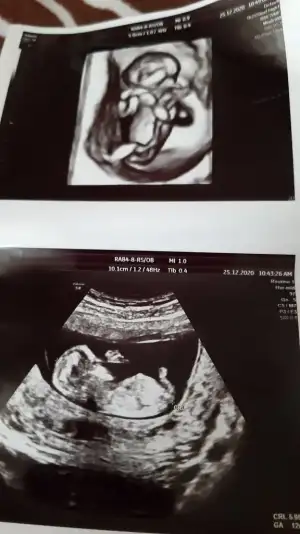

Eklentiler

• 20210116_095248.webp

20210116_095248.webp

30,7 KB · Görüntüleme: 64